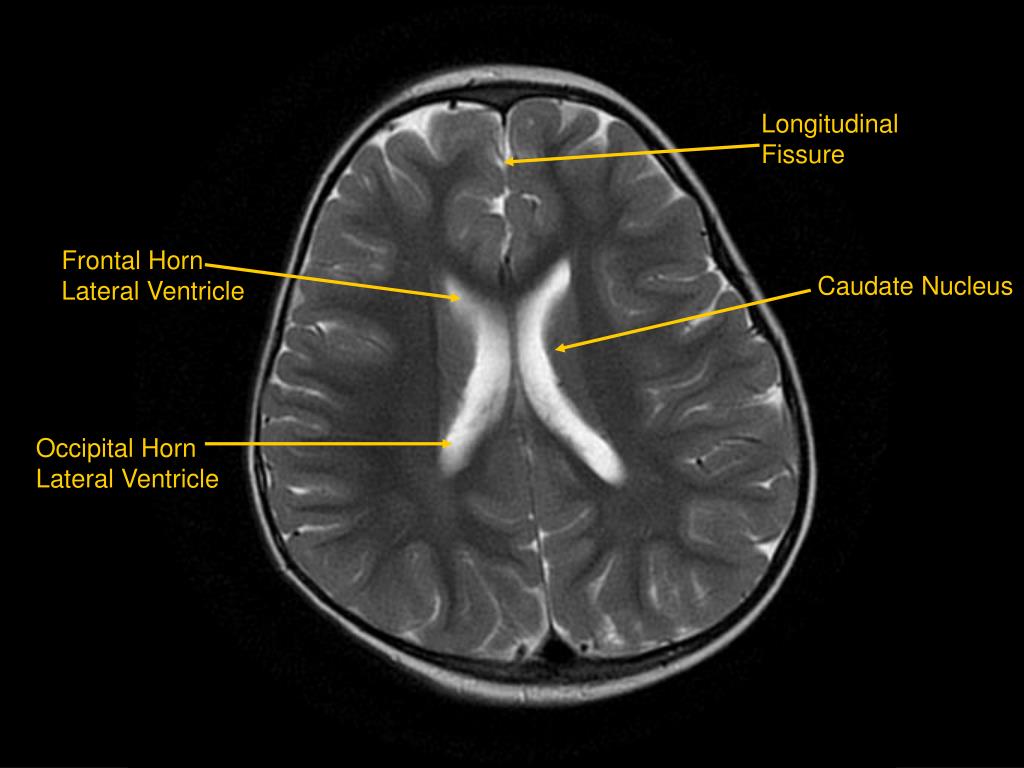

Brain Ventricles Labeled Mri . The third ventricle is located between the thalami and below the fornix of the brain. There are four such hollow spaces in the brain that house cerebrospinal fluid (csf): Two lateral ventricles, a third ventricle and a fourth ventricle. The ventricular system in the brain is a series of interconnecting spaces and channels within the brain composed of cerebrospinal fluid. The cerebral ventricular anatomy is labeled. Note, however, that mcrae’s line (basion to the.

The third ventricle is located between the thalami and below the fornix of the brain. The cerebral ventricular anatomy is labeled. Note, however, that mcrae’s line (basion to the. There are four such hollow spaces in the brain that house cerebrospinal fluid (csf): The ventricular system in the brain is a series of interconnecting spaces and channels within the brain composed of cerebrospinal fluid. Two lateral ventricles, a third ventricle and a fourth ventricle.